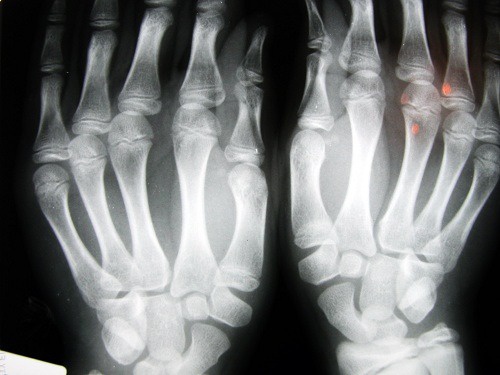

Si è provato ad analizzare diverse persone che erano solite scrocchiarsi le dita per sapere se le loro articolazioni erano danneggiate e se soffrivano di artrosi o artrite.

Quello che si è scoperto con questi studi è che le dita delle mani erano danneggiate.Molti avevano lesioni nei tessuti molli e meno forza nell’afferrare gli oggetti. Questo sembra essere collegato allo stirare e contrarre, rapidamente e in continuazione i legamenti delle articolazioni.

Un altro studio convolse 30 anziani di un ospizio di Los Angeles. Coloro che si erano scrocchiati le dita durante la loro vita, non soffrivano di osteoartrite. In un terzo studio, fatto su adulti di 45 anni di Detroit, si scoprì che il problema riguardava l’afferrare, che era meno forte e inoltre, in più dell’ 80% dei casi, soffrivano di gonfiore alle mani.